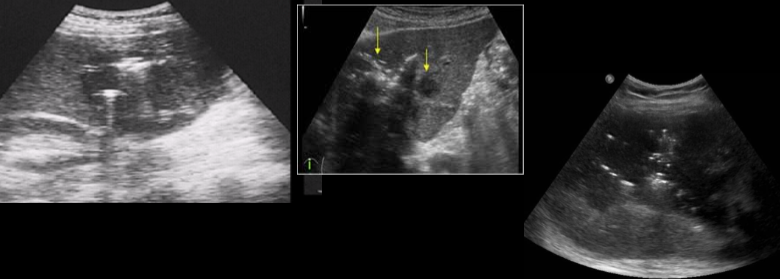

pyogenic abscess

ameobic abscess

echinococcal cyst